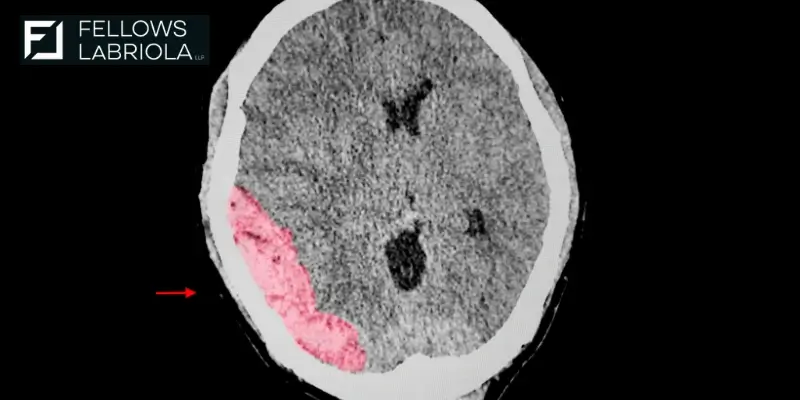

A traumatic brain injury in a legal claim is proven using medical records, brain scans, and testimony from doctors. In some cases, specialists can explain how the injury affects your memory, speech, or behavior. It’s also important to show how the injury happened and how it changed your life. The more clearly the impact is documented, the stronger the claim.